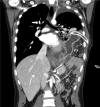

Diagnosis: CDH and iatrogenic gastric perforation by chest tube were diagnosed by chest computed tomography scan.

Interventions: The patient was transferred to our hospital immediately, and emergent operation was performed. There was a large hernial defect on the left posterolateral side of the diaphragm and various intra-abdominal organs, including the stomach, had been displaced into the thoracic cavity. After manual reduction, stomach perforation by chest tube was identified. Wedge resection of the gastric perforation site was performed and the hernial defect in the diaphragm was closed with Gore-Tex mesh and nonabsorbable sutures.